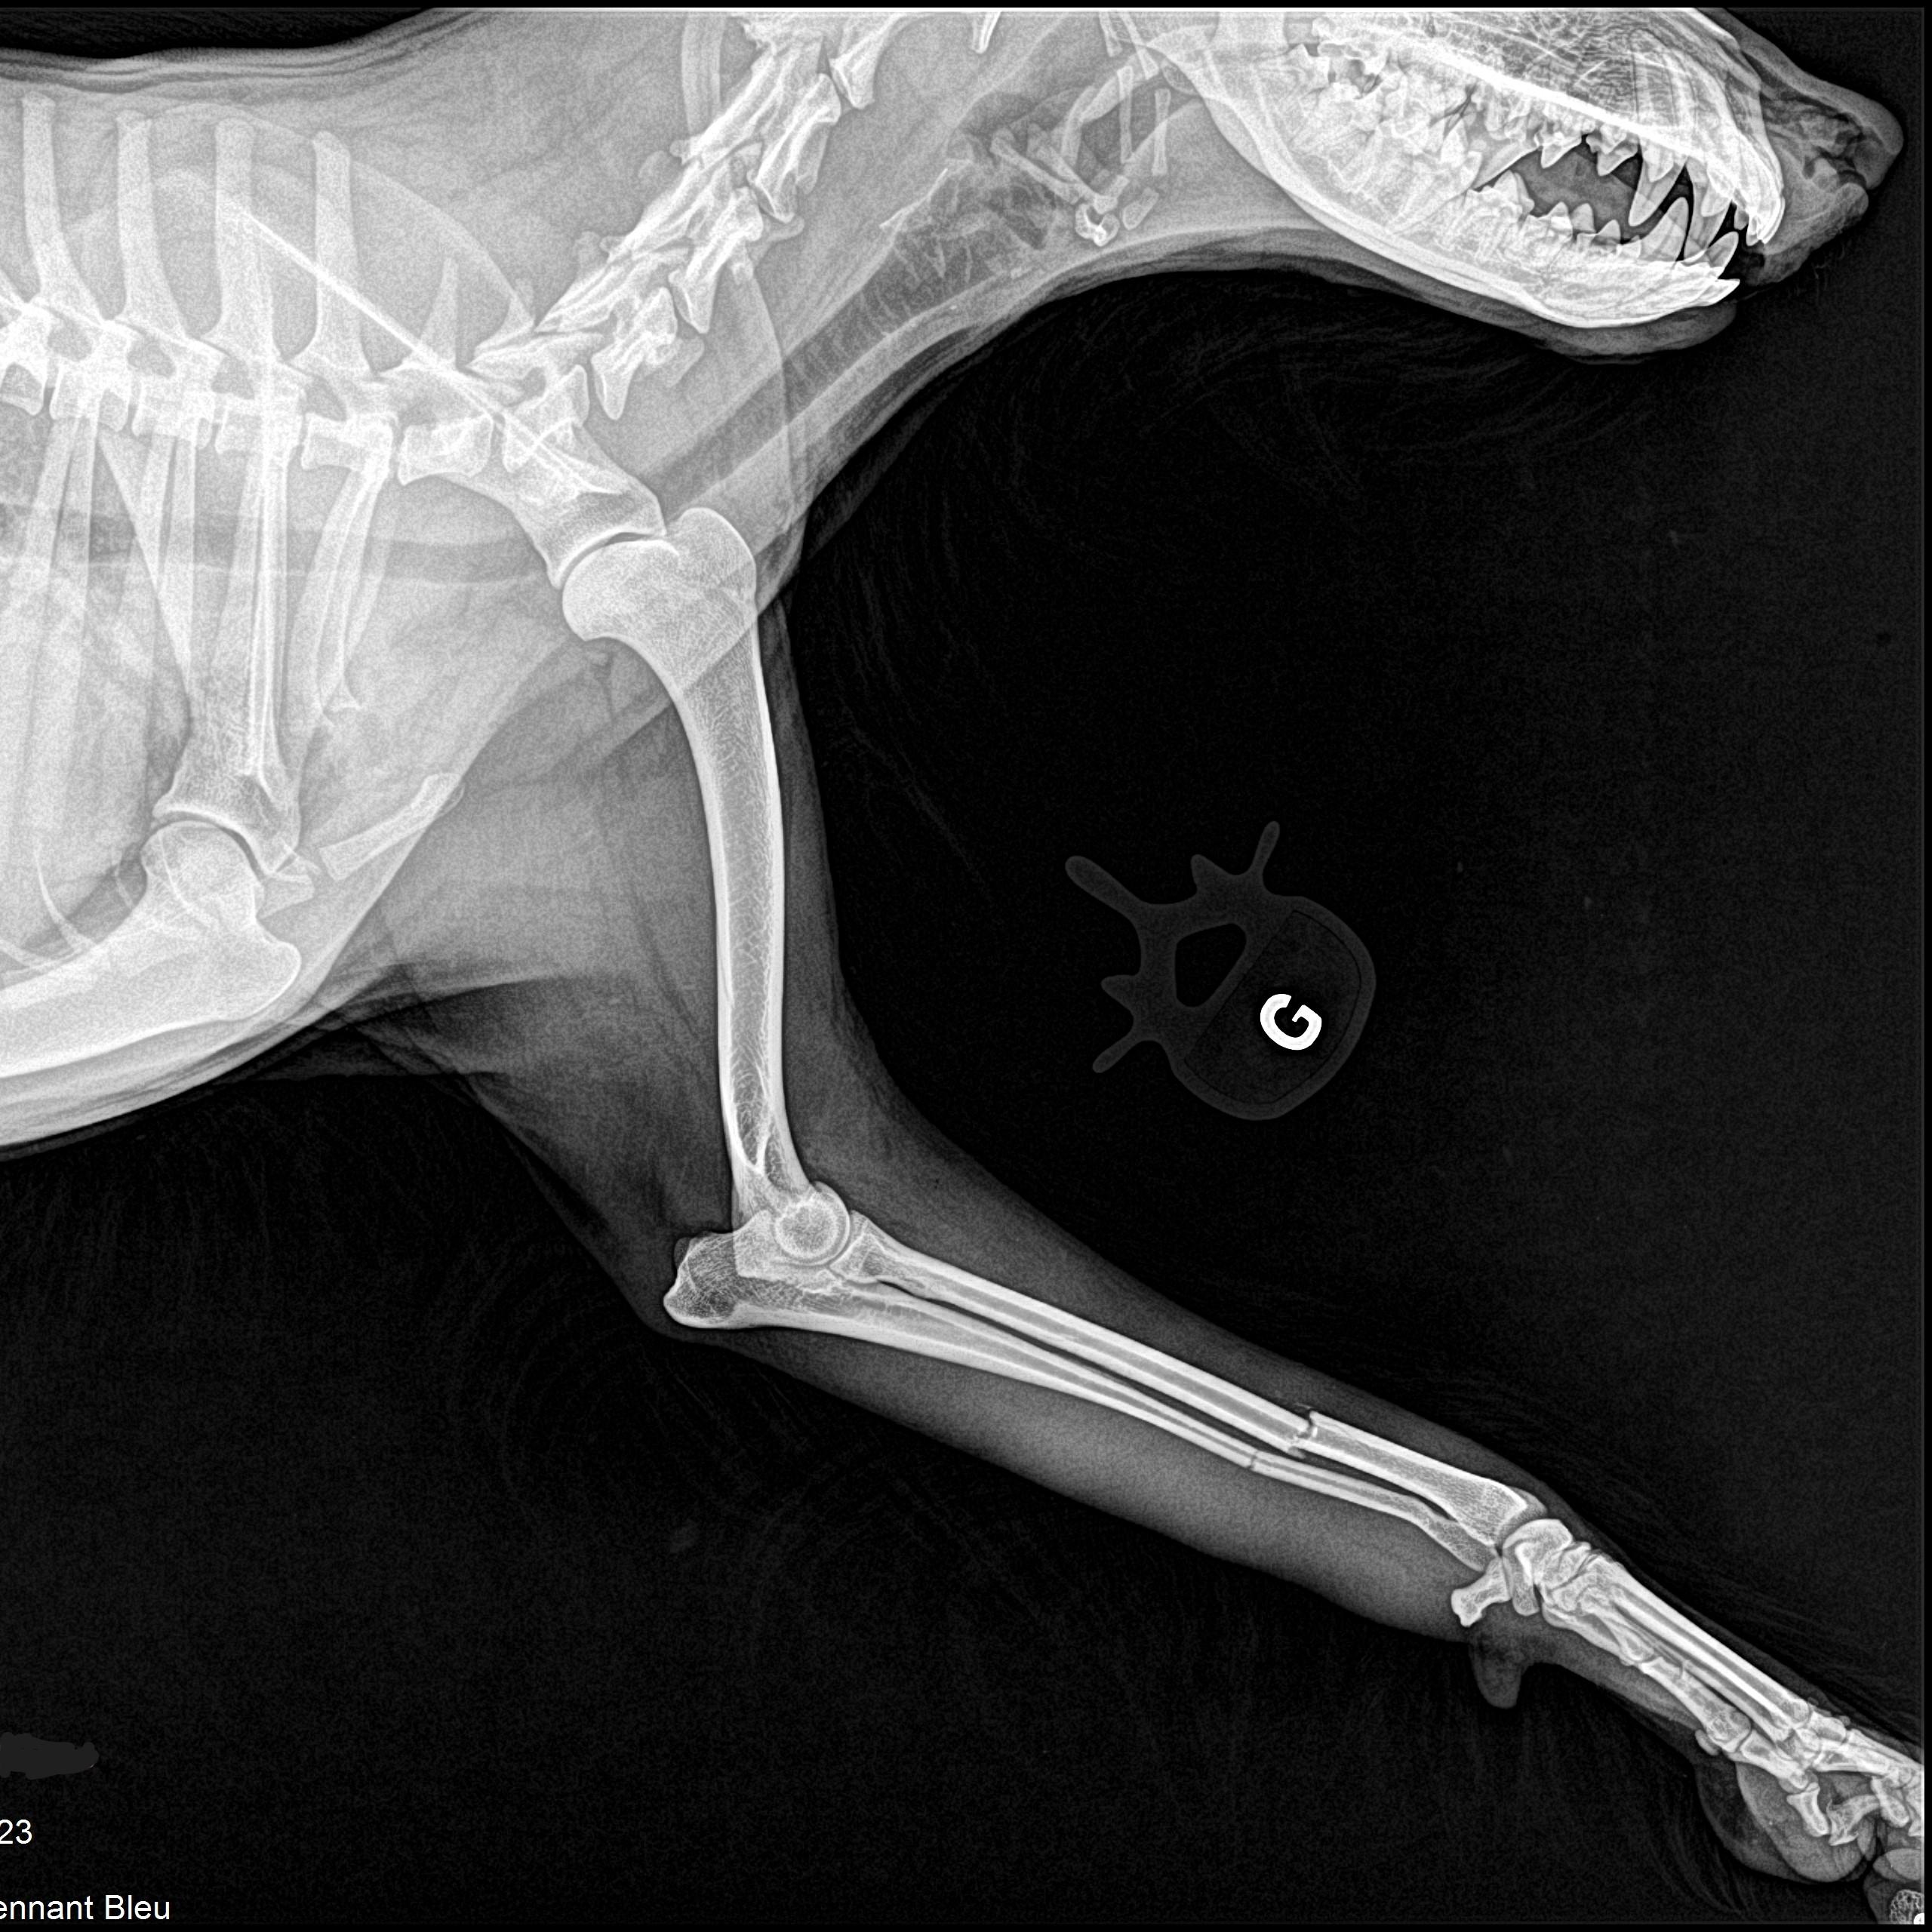

Radiographie des membres

Très utile lors de la recherche de fractures, la radiographie des membres permet également l'évaluation de différents problèmes articulaires tels que l'arthrose ou la dysplasie.

fracture d'un membre antérieur d'un chien